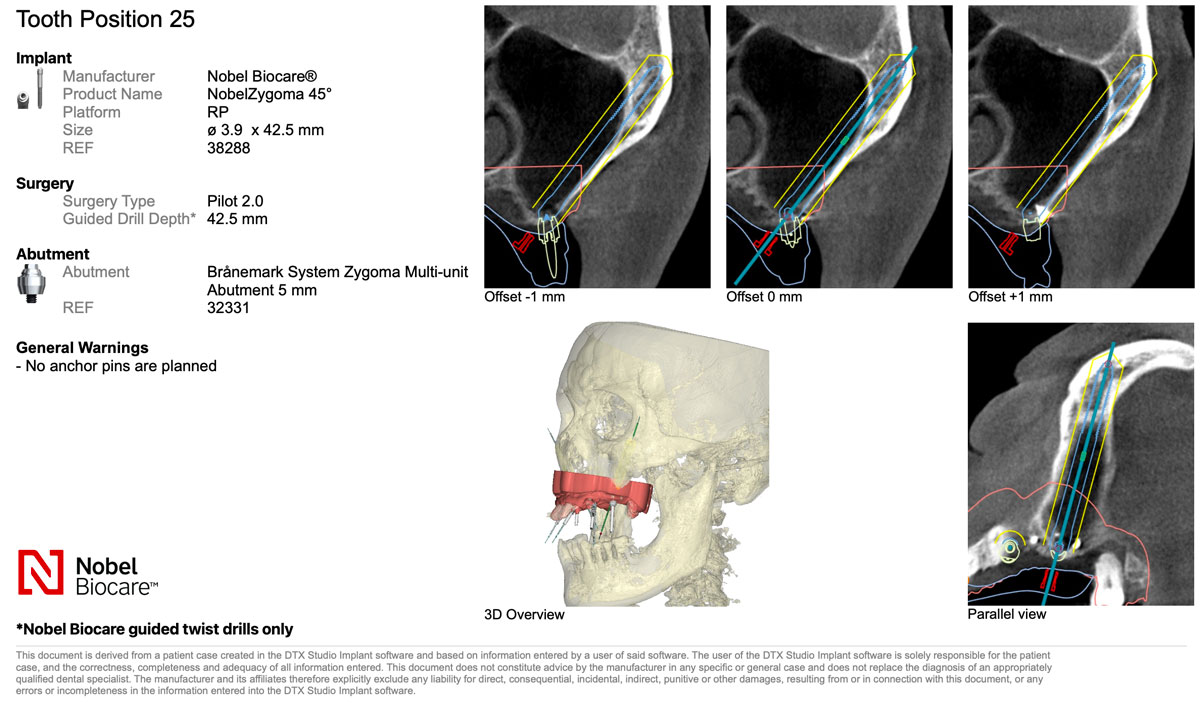

不過,顴骨植牙屬於技術門檻極高的手術,植體需穿越萎縮的上顎骨,固定在堅硬的顴骨。

長達 30~52mm 的植體比傳統更長,雖然支撐力更強,但對醫師操作的精準度要求極高。

Zygomatic implants are considered one of the most technically demanding procedures in implant dentistry. The implant, often measuring 30 to 52 mm, must traverse the resorbed maxillary bone and anchor securely into the dense zygomatic bone. While this provides strong and stable support, it also requires an exceptional level of surgical precision and anatomical understanding.

因此蒔美由口腔顎面外科專科醫師錢世康親自執刀,口外專科是牙科中處理複雜手術的權威領域,

對顎骨與顏面部解剖有深厚掌握,而顴骨植牙更是錢醫師多年臨床中最擅長的專業之一。

不同於一般診所僅拍攝局部影像,蒔美採用高階全頭顱 CT 掃描,

完整呈現從頭頂到下巴的顏面立體結構,確保醫師能精準避開所有風險區域。

同時,蒔美引進國際頂尖的 X-Guide 藍光導航系統,能即時追蹤鑽針與植體位置,確保落點毫釐不差,並縮小傷口、降低不適。

這次重建,上顎 All-on-5採用享譽全球、臨床表現卓越的諾保科Nobel Biocare植體,下顎缺牙部位則選用精密穩定、以創新聞名的士卓曼Straumann植體。

Smile Dental Group used Nobel Biocare implants—renowned worldwide for clinical excellence—for the upper jaw, and Straumann implants—celebrated for precision and durability—for the lower.